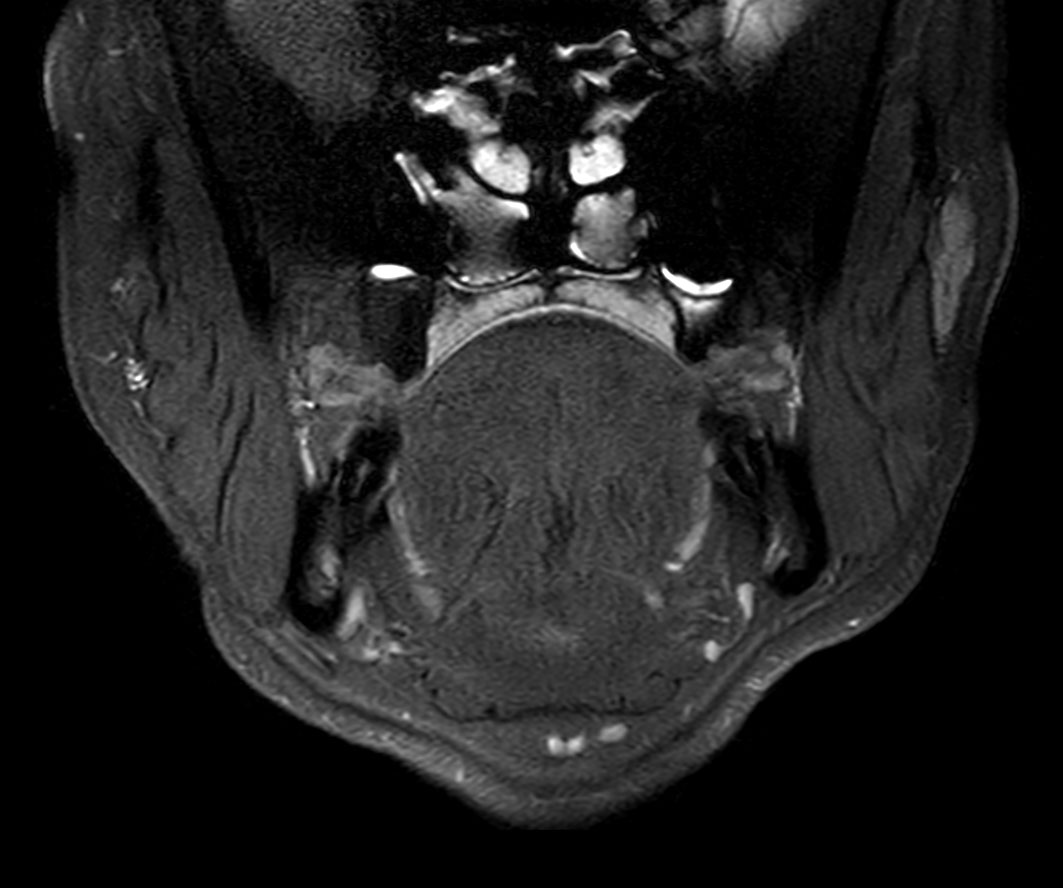

Axial STIR TSE